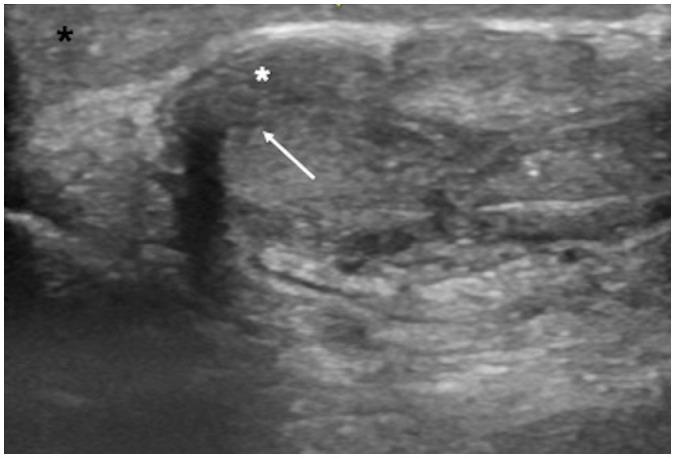

Penile emergencies are uncommon and can be categorized as having infectious, vascular, traumatic, or multifactorial etiologies. To facilitate early diagnosis and treatment during emergency, US and color Doppler imaging are imperative. US depicts hypoechoic collections regardless of the presence of air foci in infections like abscess and Fournier's gangrene. Color Doppler imaging is conducted to evaluate vascular conditions such as penile Mondor disease (PMD) and priapism. PMD is indicated by the absence of color flow and non-compressibility of dorsal penile vein. Priapism can be categorized based on cavernosal artery flow: high flow and low flow. In traumatic injuries like penile fracture, US reveals breach in tunica albuginea with hematoma. Peyronie's disease can be multifactorial in origin and the imaging is commonly visualized as thickening of the tunica albuginea and echogenic calcified plaques. Urethral injuries are urethral discontinuity with adjacent collection. Urethral calculus is visualized as echogenic focus with posterior acoustic shadowing. Therefore, effective collaboration between radiologists and urologists is required for appropriate initial diagnosis and prompt treatment.

阴茎急症并不常见,可分为感染性、血管性、创伤性或多因素病因。为便于在急诊时进行早期诊断和治疗,超声(US)和彩色多普勒成像必不可少。在诸如脓肿和福尼尔坏疽等感染中,无论是否存在气灶,超声均能显示低回声液性聚集。进行彩色多普勒成像以评估血管状况,如阴茎蒙多氏病(PMD)和阴茎异常勃起。阴茎蒙多氏病表现为阴茎背静脉无血流信号且不可压缩。阴茎异常勃起可根据海绵体动脉血流分为:高流量型和低流量型。在阴茎骨折等创伤性损伤中,超声显示白膜破裂并伴有血肿。佩罗尼氏病的病因可能是多因素的,影像学表现通常为白膜增厚和回声增强的钙化斑块。尿道损伤表现为尿道连续性中断并伴有相邻液性聚集。尿道结石表现为伴有后方声影的回声增强灶。因此,放射科医生和泌尿外科医生之间需要有效协作,以进行恰当的初步诊断和及时治疗。